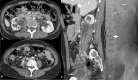

The purpose is to discuss abdominal tuberculosis mimicking malignancy involving the abdominal viscera. TB of the abdominal viscera is common, especially in countries where tuberculosis is endemic and in pockets of non-endemic countries. Diagnosis is challenging as clinical presentations are often non-specific. Tissue sampling may be necessary for definitive diagnosis. Awareness of the early and late disease imaging appearances of abdominal tuberculosis involving the viscera that can mimic malignancy can aid detecting TB, providing a differential diagnosis, assessing extent of spread, guiding biopsy, and evaluating response.